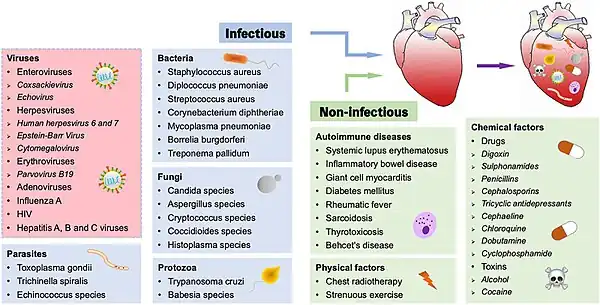

Causes

A large number of causes of myocarditis have been identified, but often a cause cannot be found. In Europe and North America, viruses are common culprits. Worldwide, however, the most common cause is Chagas' disease, an illness endemic to Central and South America that is due to infection by the protozoan Trypanosoma cruzi.[11] In viral myocarditis, the Coxsackie B family of the single-stranded RNA viruses, in particular the plus-strand RNA virus Coxsackievirus B3 and Coxsackievirus B5 are the most frequent cause.[18] Many of the causes listed below, particularly those involving protozoa, fungi, parasites, allergy, autoimmune disorders, and drugs are also causes of eosinophilic myocarditis.

Infections

- Viral (adenovirus, parvovirus B19, coxsackie virus, rubella virus, polio virus, Epstein-Barr virus, hepatitis C, and severe acute respiratory syndrome coronavirus 2)[19][20]

- Protozoan (Trypanosoma cruzi causing Chagas disease and Toxoplasma gondii)

- Bacterial (Brucella, Corynebacterium diphtheriae, gonococcus, Haemophilus influenzae, Actinomyces, Tropheryma whipplei, Vibrio cholerae, Borrelia burgdorferi, leptospirosis, and Rickettsia, Mycoplasma pneumoniae)

- Fungal (Aspergillus)

- Parasitic (ascaris, Echinococcus granulosus, Paragonimus westermani, schistosoma, Taenia solium, Trichinella spiralis, visceral larva migrans, and Wuchereria bancrofti)

Bacterial myocarditis is rare in patients without immunodeficiency.

Toxins

- Drugs, including alcohol, anthracyclines and some other forms of chemotherapy, and antipsychotics, e.g., clozapine, also some designer drugs such as mephedrone[21]

Immunologic

- Allergic (acetazolamide, amitriptyline)

- Rejection after a heart transplant

- Autoantigens (scleroderma, systemic lupus erythematosus, sarcoidosis, systemic vasculitis such as eosinophilic granulomatosis with polyangiitis, and granulomatosis with polyangiitis, Kawasaki disease, idiopathic hypereosinophilic syndrome)[22]

- Toxins (arsenic, toxic shock syndrome toxin, carbon monoxide, or snake venom)

- Heavy metals (copper or iron)

Physical agents

- Electric shock, hyperpyrexia, and radiation